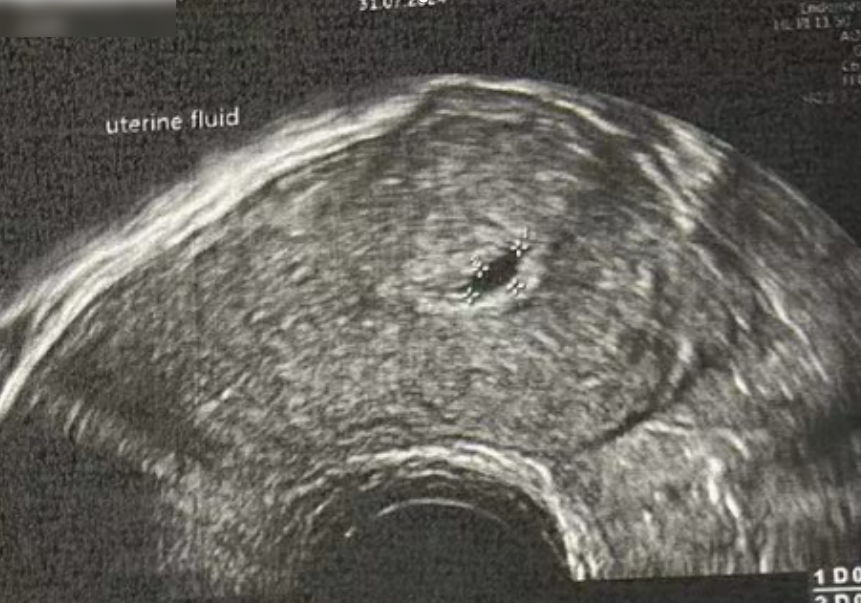

子宫内膜厚度:4.6 毫米,子宫有瘢痕大小 0.76*0.19 厘米

• Pre-Irrigation灌洗前: